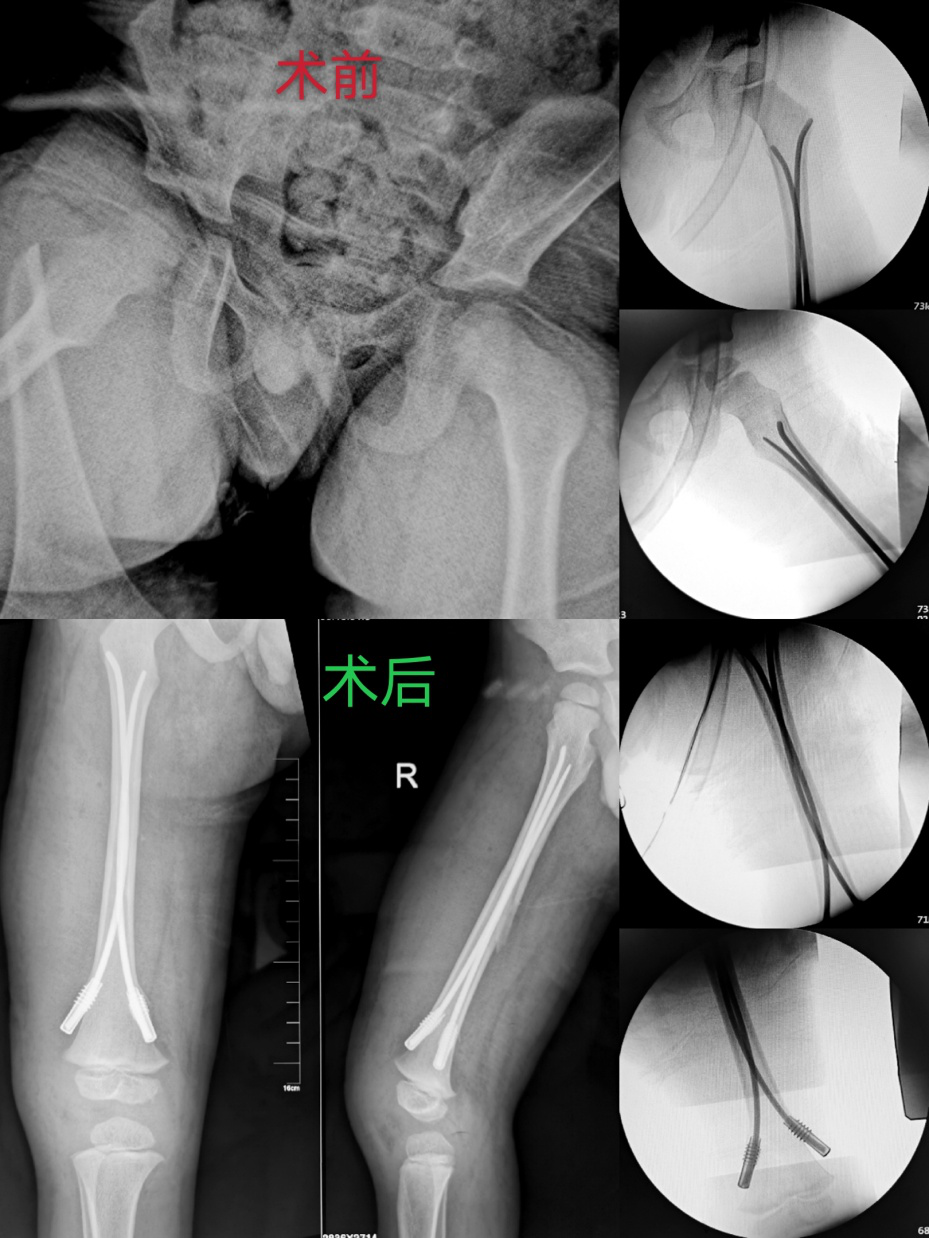

患儿,男性,4岁,以“奔跑时摔倒致右大腿肿痛伴活动受限3小时”入院。入院诊断显示右股骨干骨折。入院查体发现患儿右侧大腿肿胀明显,并呈内收成角畸形,压痛(+),末梢血运及感觉无异常,患肢X线片提示右股骨干骨折(长斜形骨折)。在全面的病情评估和术前讨论后,陈永刚与舟曲县人民医院骨科团队制定了详细周密的手术计划,于6月23日成功实施手术。

弹性髓内钉内固定是一种安全、简便、快速的儿童长骨干骨折的手术治疗方法,特别适合于治疗儿童股骨干骨折。弹性髓内钉作为一种新型的内固定材料在治疗儿童长管状骨骨折方面具有独特的优势,是符合儿童骨骼生理解剖的一种内固定方法,其手术适应证为横形、短斜形和短螺旋形等稳定股骨干骨折。

采用弹性髓内钉联合尾帽技术微创内固定治疗儿童不稳定股骨干骨折更具有优势,可有效维持骨折端的稳定,降低弹性髓内钉退钉、骨折复位丢失及股骨短缩等风险。但由于此技术对手术医师操作技术要求较高,加之由于儿童手术风险较大等原因,目前大多数基层医院小儿骨科发展较为缓慢,很多有难度的小儿骨科手术业务并未顺利开展。此例手术为舟曲县人民医院首例,也为甘南州首例。